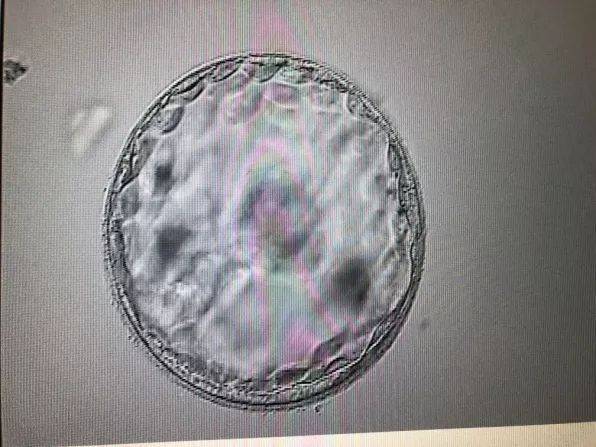

- 胚胎是什么样子图片 四周胚胎是什么样子的05-24